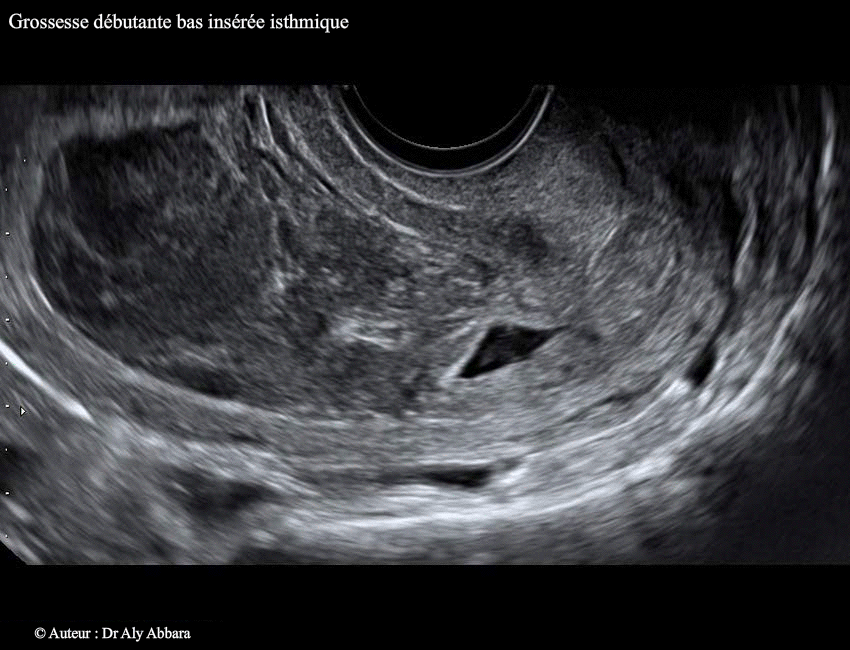

• Images échographiques montrant l'évolution spontanée d'une grossesse débutante à insertion basse, dans la zone isthmique de la cavité utérine (grossesse isthmique utérine).

• Échographiquement on peut observer à travers les images ci-dessus que le sac gestationnel qui s'est implanté dans la région isthmique de la cavité utérine continue à évoluer lors du contrôle, à 2 jours et à 4 jours après l'examen initial, avec l'apparition d'une image embryonnaire munie d'une activité cardiaque et mesurant, à J4, 2,3 mm.

Le sac gestationnel était partiellement décollé au niveau de son pôle supérieur dès l'examen initial. Ce décollement s'élargissait à J2 et à J4 ; il est à l'origine (dès l'examen initial) de la formation d'une hématométrie qui s'aggravait au cours du développement de la grossesse (36 ml à J4 et 47 ml à J6) ; deux éléments participaient à sa formation : le décollement progressif du sac gestationnel et l'effet de bouchon exércé par ce sac sur le canal cervical en l'obstruant au niveau de son orifice interne.

A J6 : on observe l'arrêt de l'activité cardiaque embryonnaire et l'écrasement du sac gestationnel et son engagement partiel dans le canal cervical sous l'effet des contractions utérines et la pression exercée par la volumineuse hématométrie.